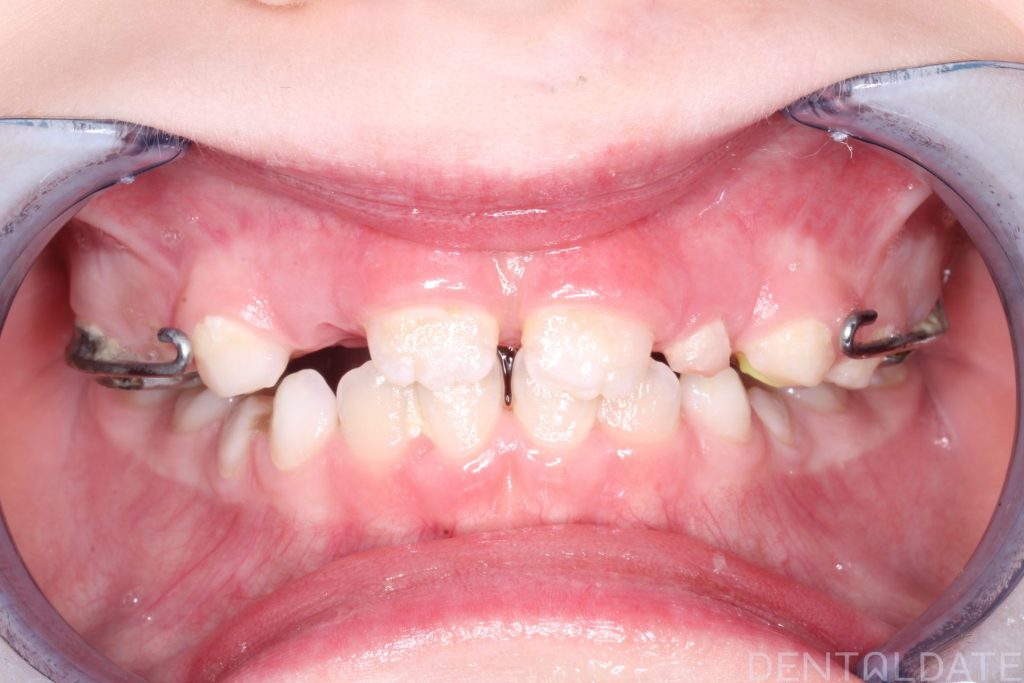

We placed a Haas appliance and supported it with a Delaire facemask.

The young patient is now able to chew comfortably and smile with confidence.